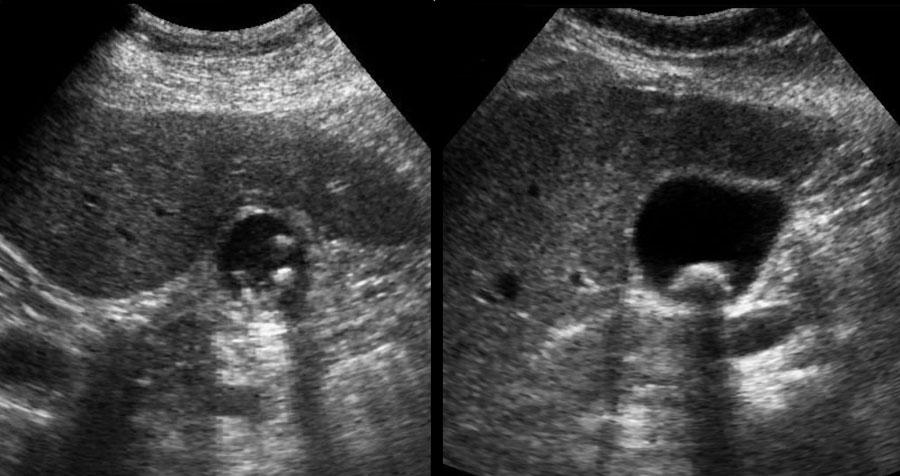

Dưới đây là hai ví dụ về sỏi kẹt được phát hiện trong cơn đau quặn mật ở các bệnh nhân khác nhau.

Ở tư thế nằm ngửa, một viên sỏi (mũi tên) được phát hiện tại cổ túi mật.

Sau khi đứng dậy, cúi người và đi lại, viên sỏi (mũi tên) không di chuyển xuống, do đó phải là sỏi kẹt.

Sỏi trong ống túi mật đôi khi không thể hiển thị được trên mặt phẳng siêu âm theo trục dọc của túi mật.

Hình ảnh của một bệnh nhân bị phình to túi mật cấp tính do sỏi kẹt.

Sỏi kẹt không thể hiển thị được trên trục dọc của túi mật, do vị trí nằm ở phía trong của ống túi mật (mũi tên).